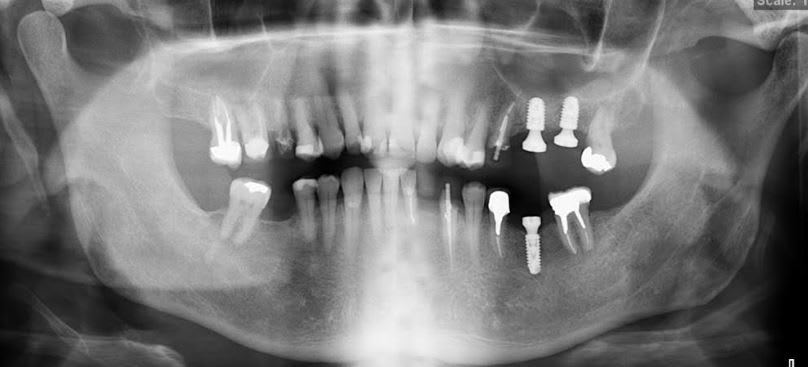

Identification implant

Bonjour je n'ai pas de rétro

Merci de m'aider à identifier les implants .

pas de bras, pas de chocolat

pas de rétro, pas d'identification possible à 100%

donc je préfère me taire que de te dire une connerie, même si j'ai une bonne idée de ce que çà peut être comme implant....